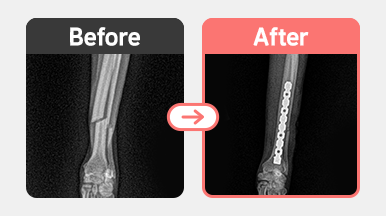

[요골 골절 수술] 말티푸 / 1살 / 우측 radius 횡골절 / plate 내고정술

2025-11-13